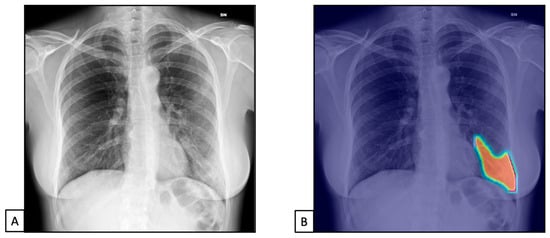

3.3. Typical Bacterial Pneumonia

To test the most experienced radiologist and the AI system regarding COVID-19 pneumonia, we used CXRs belonging to datasets 2 and 3 (n = 1500).

The TPs and TNs, according to the radiologist, were similar to the AI system ones [n = 1218 (81.2) and n = 235 (15.6), and n = 1191 (79.4) and n = 234 (15.6), respectively], both with similar FPs and FNs [n= 127 (5.9) for both, and n = 60 (2.8) and n = 79 (3.7), respectively]. This resulted in 97.9% sensitivity (98.0–99.3) and 88% specificity (83.5–91.7) for the radiologist and 97.5% sensitivity (96.5–98.3) and 83.9% specificity (79.0–87.9) for the AI system (Figure 4 and Figure 5).

Figure 4.

Chest X-rays of patients admitted to the emergency department with respiratory distress and fever belonged to dataset 2. (A) represents CXR acquired at the bedside, showing compact typical opacities in the left lung lower zones. (B) represents AI system analysis, showing the pathological zones. The AI system reported a high suspicion of pneumonia, not typical for COVID-19 (99.99%). The final diagnosis was lung pneumonia due to Streptococcus pneumoniae.

The radiologist showed 97.4% PPV (96.5–98.1) and 94% NPV (90.4–96.3), while the AI system showed 96.3% PPV (95.2–97.1) and 88.6% NPV (84.5–91.7).

Finally, the accuracy was similar between the radiologist and the AI system [96.9% (95.8–97.7) vs. 95% (93.7–96), respectively].